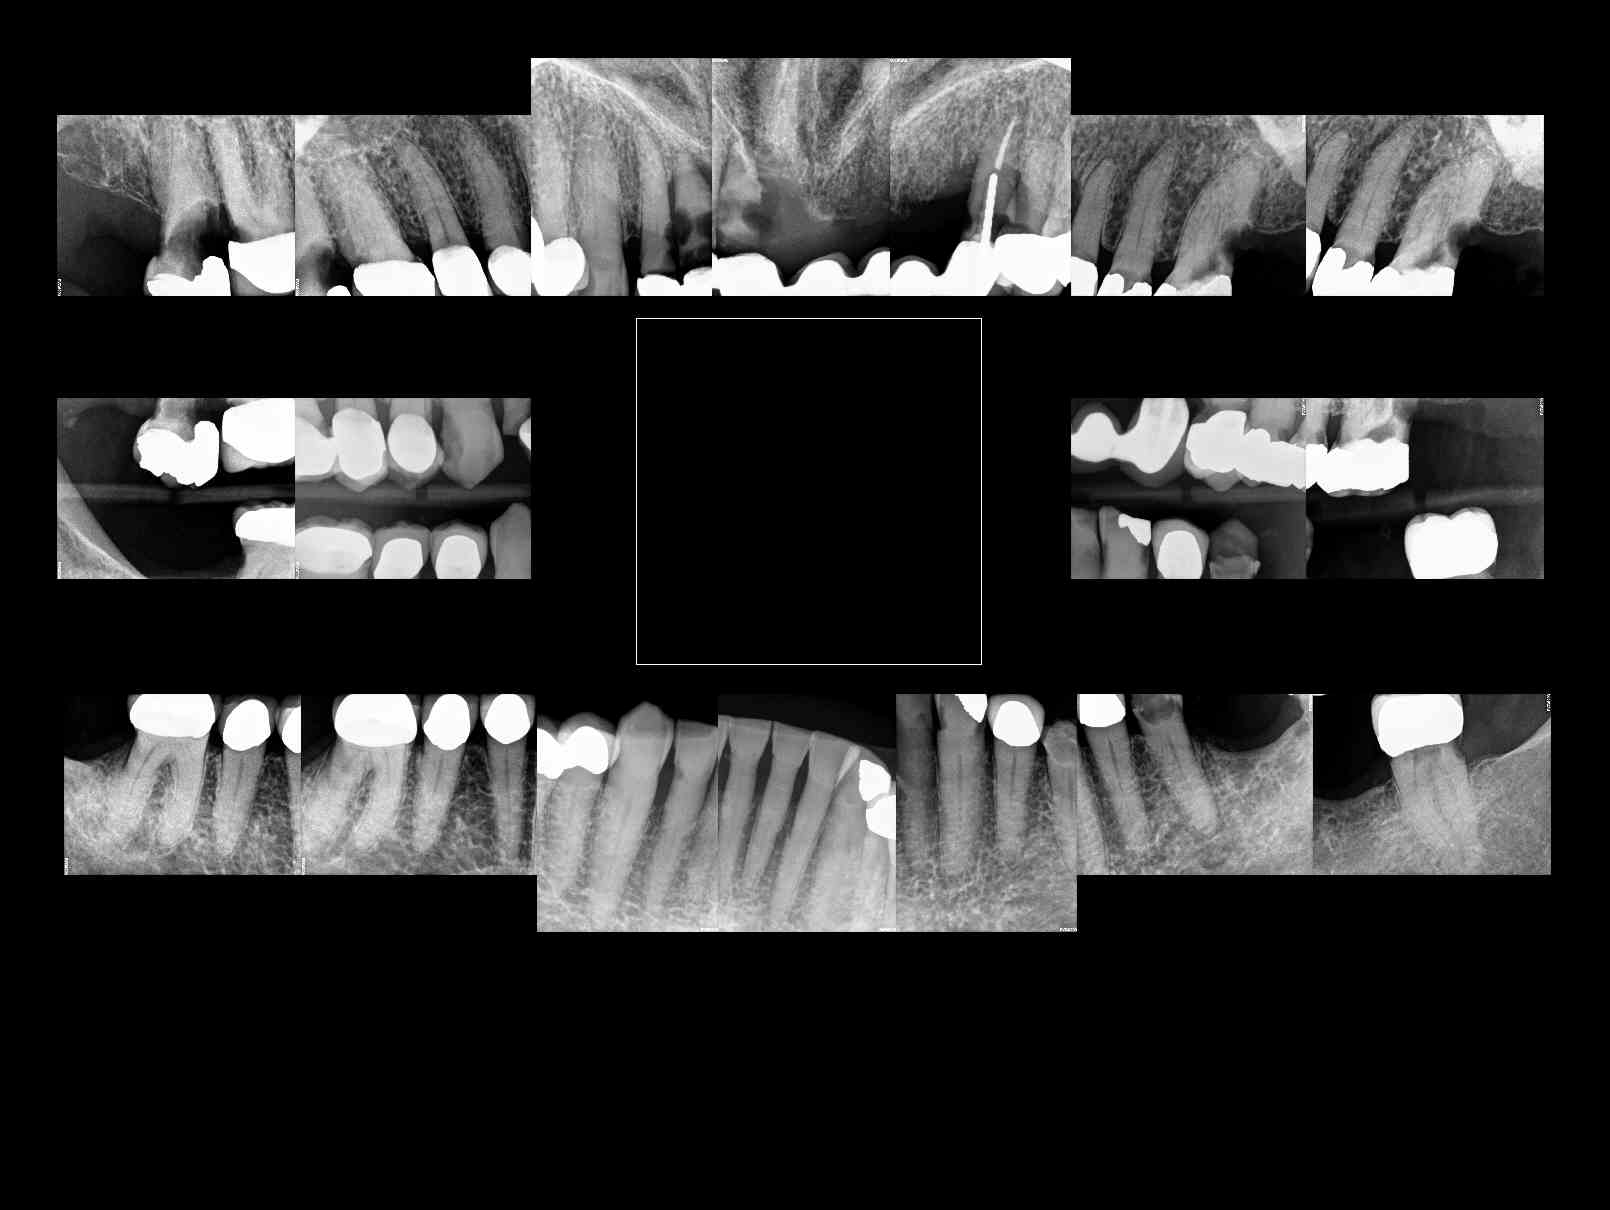

Patient requests ALL ON 4 for both upper and lower arches, complete case fee. X-rays available, taken last week

Auction images